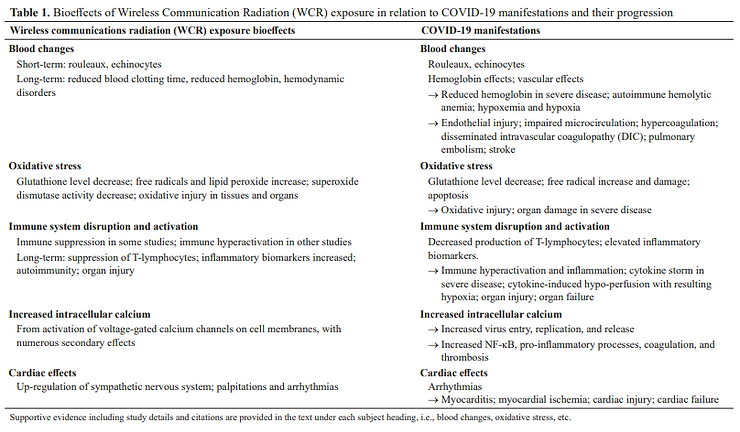

Check Out the Negative Toxic Effects of Radiation on the Human Blood!

Humanity NEEDS to know and understand the source of what is being referred to as a viral infection is in reality a transmission of directed pulsating microwave radiation that can lead to pathological coagulation, oxygen deprivation, heart failure and death! (Refer to the peer-reviewed articles below – Pathological Blood Coagulation and the Mycotoxic Oxidative Stress Test – MOST and Second Thoughts About Viruses, Vaccines and the HIV/AIDS Hypothesis)